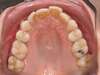

Cas N°6 : Description

Correction majeure des deux arcades dentaires liée à une mandibule rétrusive

Avant

Après